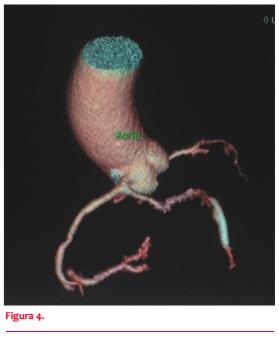

La CACG evidencia una arteria coronaria única, con origen en un ostium en el seno de Valsalva derecho y rápida división de un corto tronco común en arteria coronaria derecha (CD), descendente anterior (DA) y circunfleja (Cx) (figura 1). Tronco sin lesiones. CD dominante, con lesión severa en tercio distal. Descendente posterior con lesión severa ostial y en tercio medio. La DA, de fino calibre, tiene lesión suboclusiva en tercio medio y lesión severa distal. Cx sin lesiones. Gran ramo marginal presenta lesión severa proximal. Se realiza ATC de DA con implante de stent Minivision 2,0 mm por 2,3 mm sin incidentes.